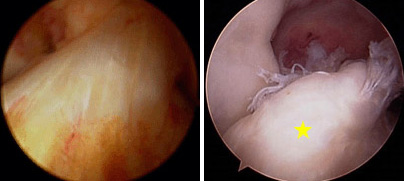

(Izquierda) Imagen artroscópica del LCA sano. (Derecha) Imagen artroscópica del LCA desgarrado (estrella amarilla).